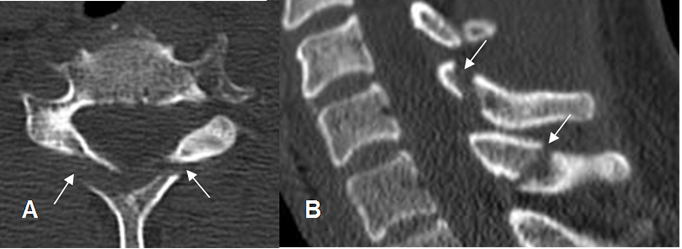

Fig 162. Fractura inestable.

A y B: TAC axial y C: TAC reconstrucción sagital. Fractura conminuta en el cuerpo vertebral, con compromiso de la columna anterior (Flecha delgada), media (Flecha gruesa) y posterior (Punta de flecha), lo que la define como radiológicamente inestable. Se aprecia fragmento retropulsado y desplazamiento anterior de la apófisis espinosa, dentro del canal.